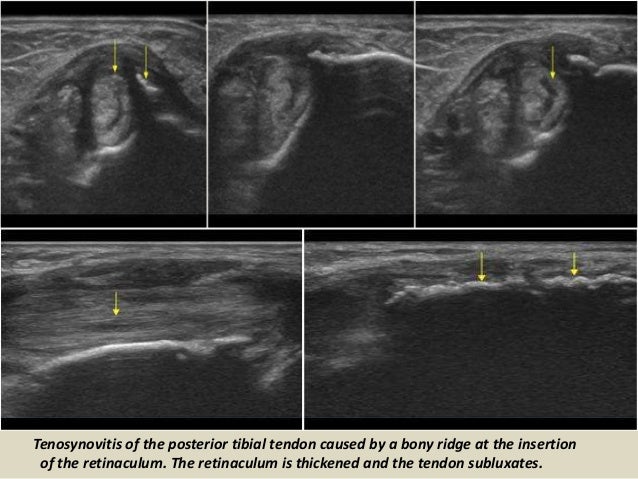

Tenosynovitis of the posterior tibial tendon caused by a bony ridge at the insertion

of the retinaculum. The retinaculum i...

54. 54. Tenosynovitis of the posterior tibial tendon caused by a bony ridge at the insertion of the retinaculum. The retinaculum is thickened and the tendon subluxates.